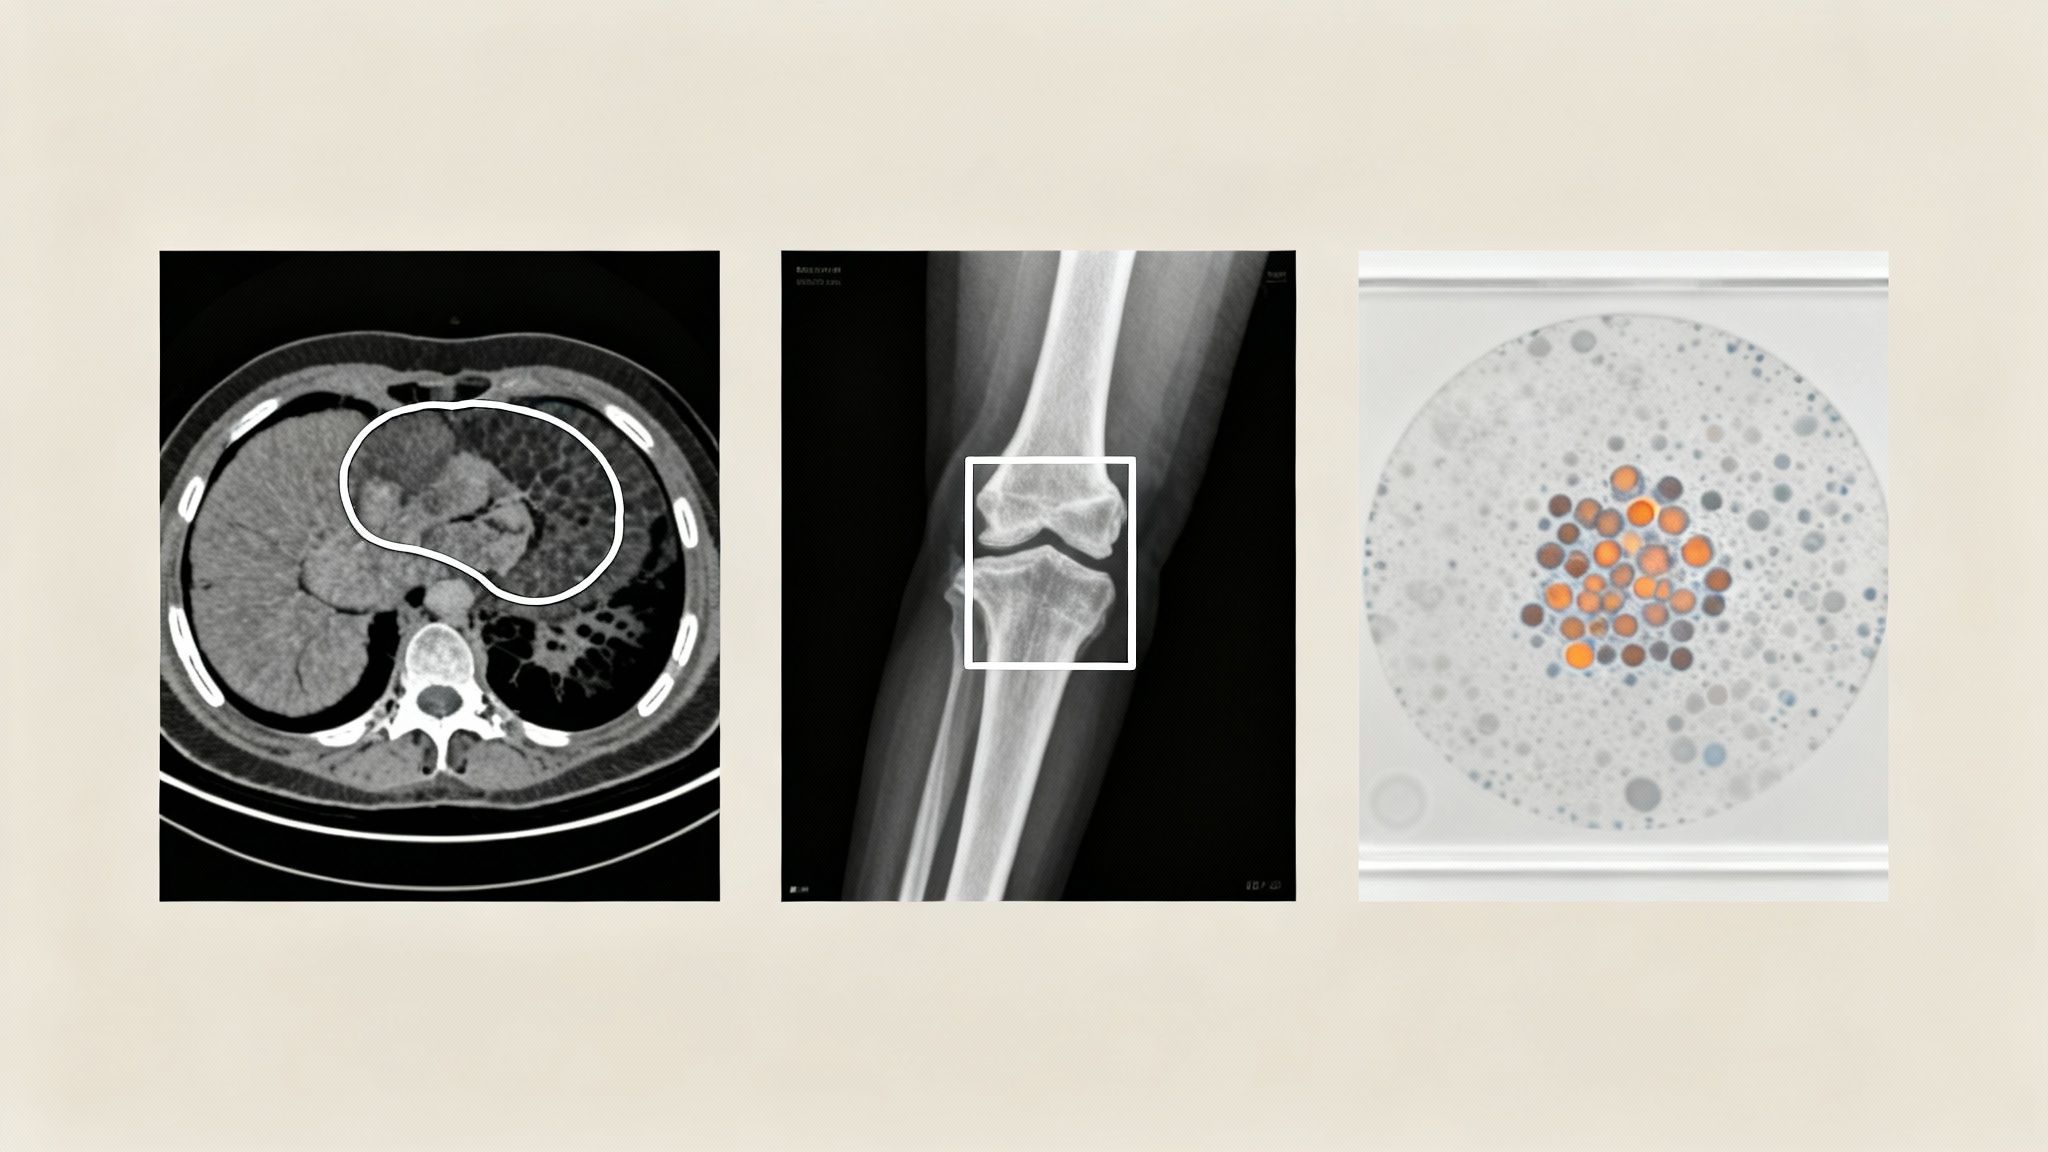

A few core techniques are used, each suited for a different diagnostic goal:

- Bounding Boxes: This is one of the most direct methods. An annotator simply draws a rectangle around an object of interest. For example, a radiologist might use bounding boxes to quickly highlight potential fractures on an X-ray, which in turn trains a model to flag similar injuries for review.

- Semantic Segmentation: This is a much more detailed approach. Instead of a simple box, semantic segmentation involves tracing the exact pixel-by-pixel border of an object. This level of precision is critical for tasks like outlining a tumor on a CT scan to measure its volume or plan a surgical procedure.

- Keypoint Annotation (Pose Estimation): This technique involves marking specific points of interest on an image. In orthopedics, for instance, an AI can be trained by placing keypoints on joints in an X-ray. This allows the model to measure angles and assess alignment, providing valuable assistance in surgical planning.

To illustrate how these annotation types connect to real-world AI applications, here is a quick breakdown.